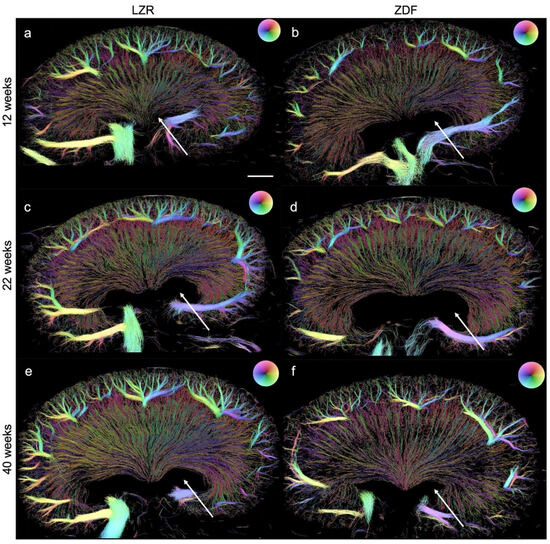

Figure 7.

SRUS images of kidneys from the Zucker diabetic fatty (ZDF) rats and the lean Zucker rats (LZRs) by weeks 12, 22, and 40. (b,d,f) illustrate a less dense renal vasculature in the ZDF rats compared with their age-matched LZR (a,c,e). Hydronephrosis (arrows) was found in all the kidneys examined. The direction of the MBs, hence the blood flow’s direction, is illustrated by the color wheel in the upper right corner, e.g., green color represents tracked MBs moving downwards, in the renal vein it correlates with blood flow out of the kidney. Scale bar in (a): 2 mm.

3.3. Quantified Measurements from SRUS

Examples of the SRUS images from each group are presented in Figure 7, showing the presence of hydronephrosis to various extents in all of the kidneys examined. The estimated mean vascular density is illustrated in Figure 8. The ZDF rats had a significantly decreased density in the CO at 22 weeks of age compared to the lean rats’ (p = 0.02). The same non-significant trend was seen at week 12 (p = 0.19). The high variance in density in the 40-week-old ZDF rats likely influenced the lack of a significant difference (p = 0.07). A significant decline in vascular density in the IM and OM of the ZDF rats was present by week 40 (p < 0.0001).